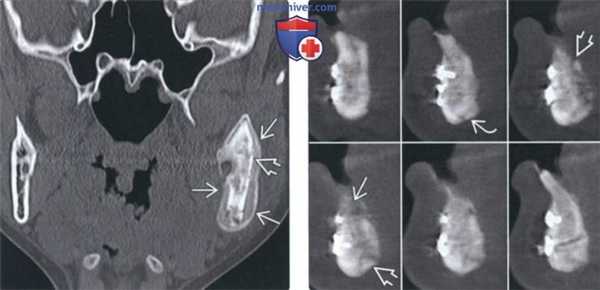

(Слева) На корональной КТ в костном окне у ребенка визуализируются обширные периостальные наложения, полностью окружающие ветвь нижней челюсти слева. Определяется частичная резорбция кортикальной пластинки нижней челюсти, которая, тем не менее, остается различимой. Также определяются деструктивные и склеротические изменения трабекулярной кости.

(Справа) На КЛКТ (профильный срез) у пациента с переломом нижней челюсти сращение отсутствует, определяется остеомиелит. Наблюдается разрежение и секвестрация язычной кортикальной плааинки, также видны периостальные наложения по нижнему краю.

4. КТ при остеомиелите челюсти:

• КТ в костном окне/КЛКТ:

о Смешанная, неровная деструкция кости и склероз:

- Острая фаза: преимущественно лизис губчатой кости с фрагментацией кортикальных пластинок

- Хроническая фаза: более выраженный склероз трабекулярной кости

о Секвестрация лучше определяется на КТ

о Периостальные наложения вдоль кортикальной пластинки:

- Увеличение челюсти можно спутать с другими заболеваниями:

Идентификация фрагментов кортикальной пластинки позволяет подтвердить, что изменения связаны с периодонтом